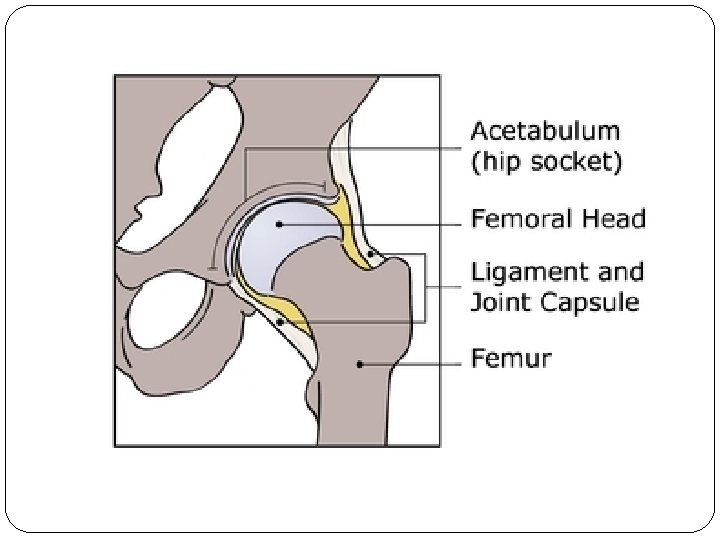

Simple Anatomy The hip is a “ball-and-socket” joint that is held together by ligaments (ligament of teres, ileofemoral, ischiofemoral, transverse ligament). The ball is called the “femoral head” which is the top of the femur or thigh bone. The socket is called the “acetabulum” and is a part of the pelvis. The femoral head fits into the acetabulum creating the hip joint. This joint is normally held tightly in place by the surrounding ligaments and joint capsule.

Cont …. Pathology: a. The acetabulum is shallow (shaped like a saucer instead of a cup). b. The femoral head gets dislocated. c. The capsule is stretched and the ligamentum teres becomes elongated and hypertrophied. Two forms of femoral dysplasia are: Coxa vara, in which the femur head grows at too narrow an angle to the shaft. Coxa valga, in which the angle is too wide.